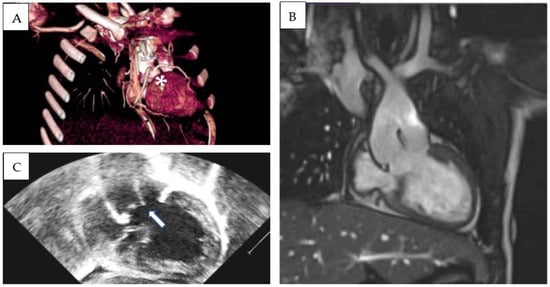

Patient 3 was diagnosed at birth with (S,D,D), DOLV with a subaortic VSD, and PS. The infundibular septum was hypoplasic. The aorta arose on the right and was posterior to the pulmonary trunk. The pulmonary artery was in fibrous continuity with the mitral valve, and a subaortic conus was present. The right coronary artery and left descending anterior artery originated from a single ostium from the anterior facing sinus. LCx was not visualized in echocardiography. A subsequent CT scan revealed that the LCx originate from the posterior-facing sinus, with a retroaortic course and slit-like origin (Figure 2). After the initial B-T shunt palliation, a Rastelli-type operation was performed at 1 year of age (10 kg), the interventricular communication was closed, and a bicuspidized pulmonary homograft was sewn in the right ventricular outflow tract. LPA was enlarged with the interposition of a Dacron patch. After a 6 year follow-up, severe degenerative stenosis of the RV-to-PA conduit was present; nevertheless, percutaneous conduit dilatation was contraindicated due to coronary abnormality. LCA and RCA were, respectively, caudal to supravalvular and subvalvular segments of the RV-to-PA conduit. After multidisciplinary discussion, an aortic homograft (25 mm) was implanted. At the last follow-up (total f.u. time 10.2 years), the patient was in good clinical status and presented moderate right ventricular outflow tract obstruction (gradient from tricuspid regurgitation at least 50 mmHg, between 50% and 75% of systemic arterial pressure). No arrhythmias were detected during follow-up, except for low-burden premature ventricular beats with superior axis and rBBB morphology, present at rest and during recovery, and disappearing with maximal exercise.

Figure 2.

Three-dimensional (A) and MPR-angio CT scan (B) documenting anomalous coronary anatomy in Patient 3. Due to the strict relationship between RV-to-PA conduit and RCA and LCA, percutaneous conduit dilatation was contraindicated.

Patient 4 was transferred from another center because of severe cyanosis (SpO2 40%). On admission, S,D,L-DOLV with subaortic VSD and PS were diagnosed. The aorta was anterior and to the left of the pulmonary artery and overrode a large conoventricular VSD. The pulmonary valve annulus was hypoplastic, and posterior deviation of the infundibular septum was evident. The mitral valve showed fibrous continuity with the pulmonary artery, and a well-developed subaortic conus was detected in 2D echocardiography (Figure 3D,E). A balloon atrial septostomy was performed to increase blood mixing, and the baby was then discharged. REV (Reparation à l’ètage ventriculaire) was performed at 1 year of age. After a follow-up period of 8.6 years, the patient showed a good clinical status. Significant pulmonary regurgitation was present at cardiac follow-up MRI (regurgitant fraction: 49%) with a mild increase in right ventricular volumes (end-diastolic volume 103 mL/m2). During periodic Holter monitoring, no significant arrhythmia was identified, except for the finding of ectopic atrial rhythm, without significant symptoms and with adequate chronotropic response during exercise stress testing.

Figure 3.

(A) 2D Echocardiographic parasternal short-axis view documenting both great arteries originating from the morphological left ventricle. (B) Echocardiographic and (C) MRI views documenting DOLV and hypoplasic right ventricle (patient 1). (D,E) Parasternal long-axis view documenting mitro-aortic discontinuity and mitro-pulmonary continuity in patient 4.